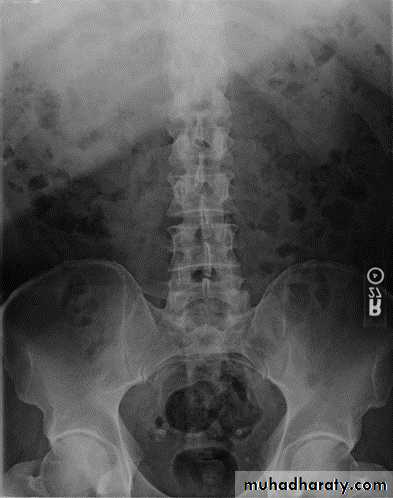

Urinary calculi

Nephrocalcinosis

Deposition of calcium salts in the medulla or cortex of the kidney.Medullary Nephrocalcinosis